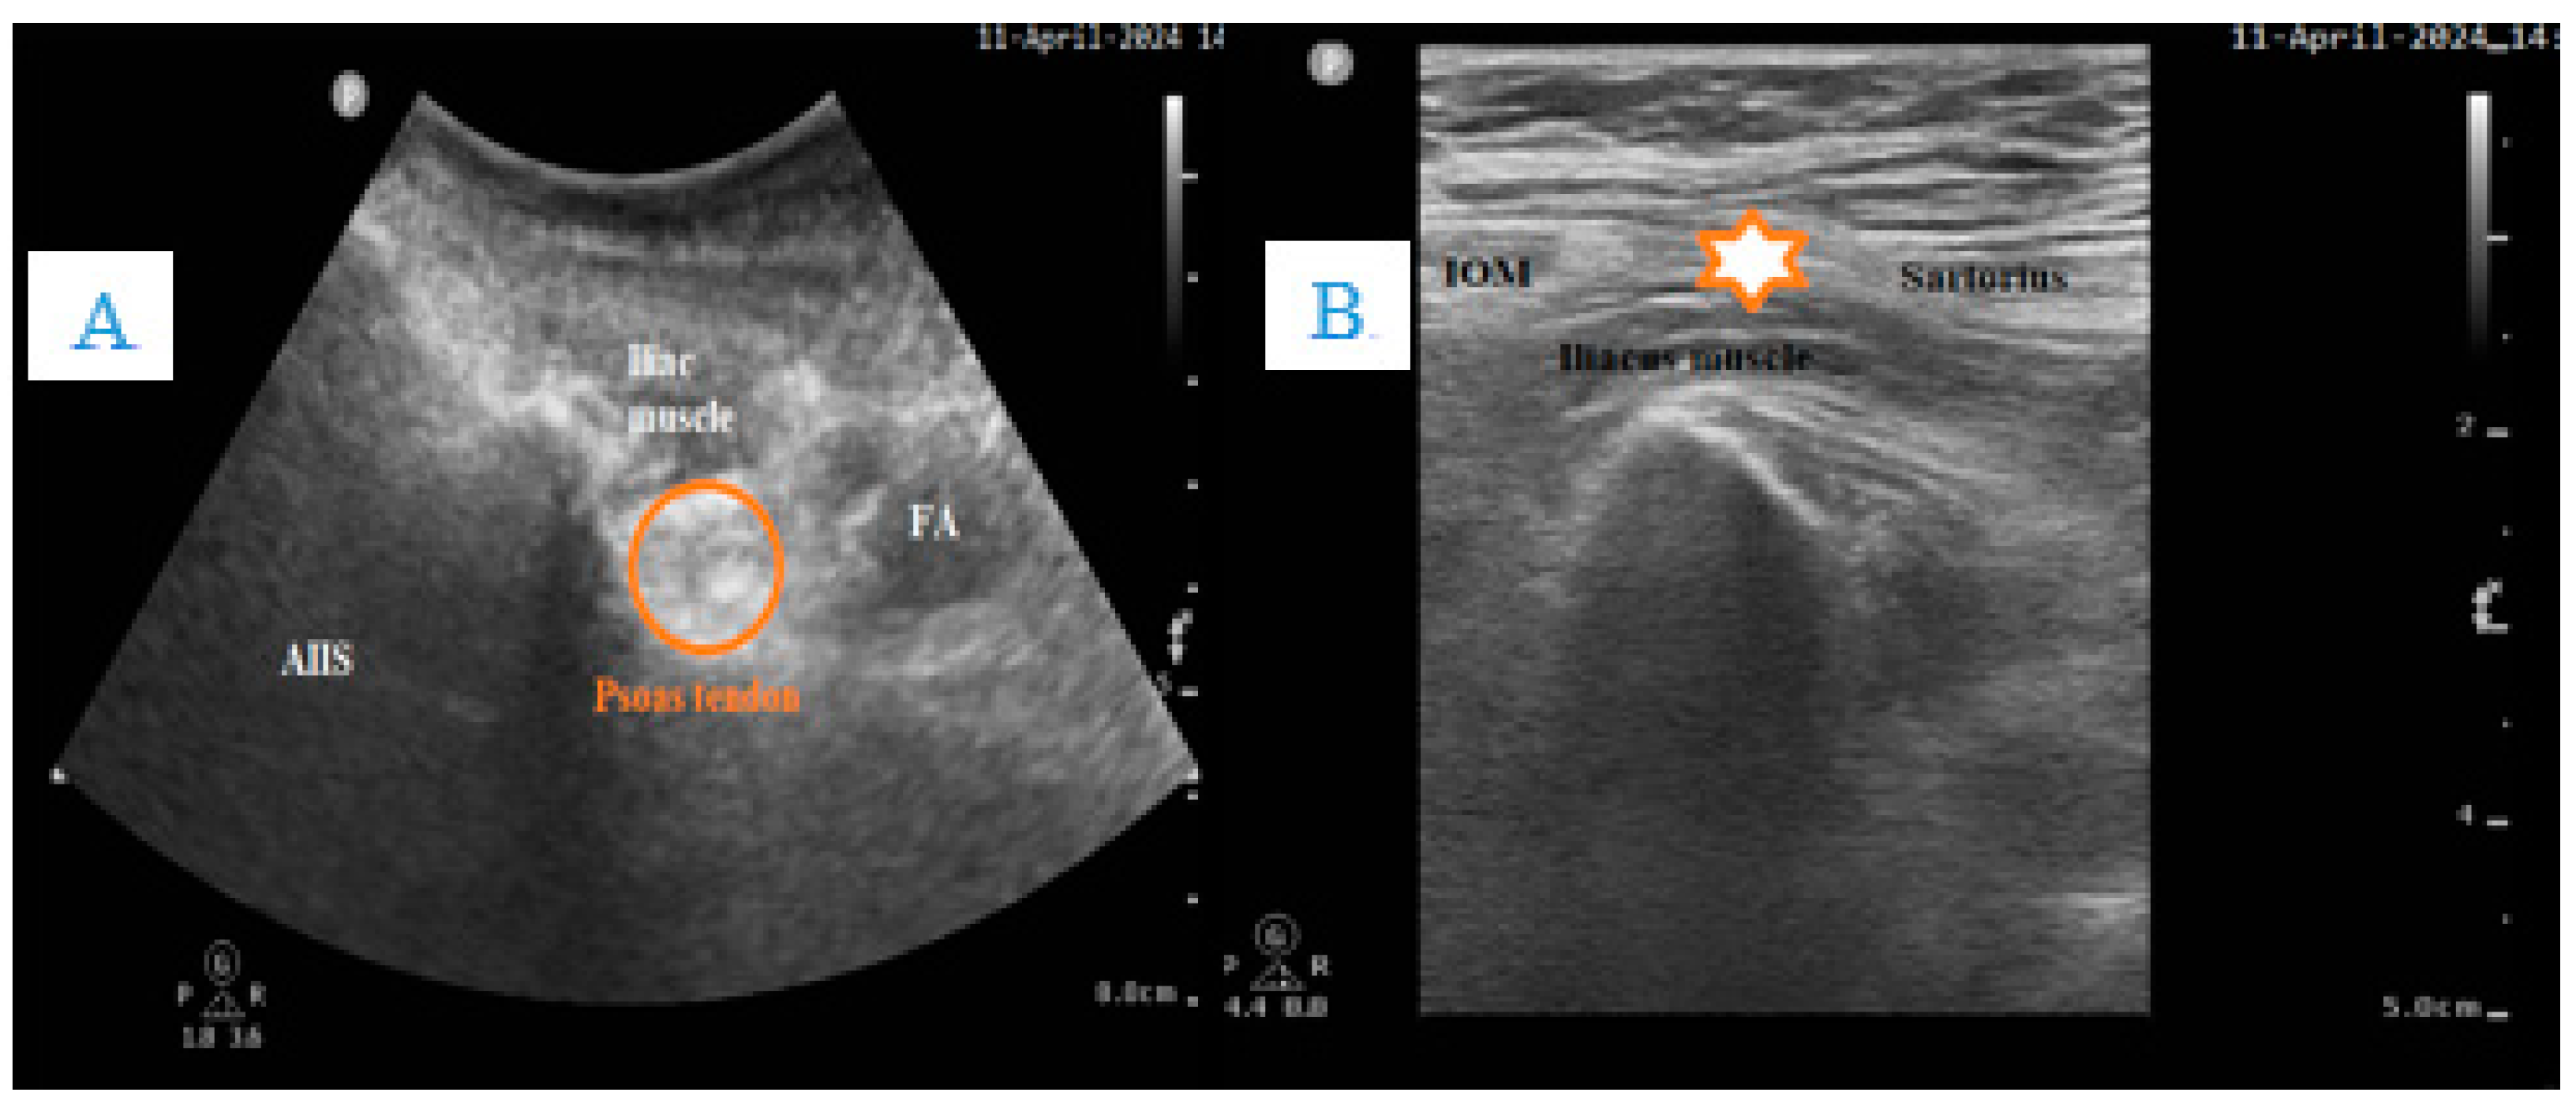

- Ketelaars, R.; Stollman, J.T.; van Eeten, E.; Eikendal, T.; Bruhn, J.; van Geffen, G.-J. Emergency physician-performed ultrasound-guided nerve blocks in proximal femoral fractures provide safe and effective pain relief: A prospective observational study in The Netherlands. Int. J. Emerg. Med. 2018, 11, 12. [Google Scholar] [CrossRef] [PubMed]

- Chen, L.; Shen, Y.; Liu, S.; Cao, Y.; Zhu, Z. Ultrasound-guided supra-inguinal fascia Iliaca compartment block for older adults admitted to the emergency department with hip fracture: A randomized controlled, double-blind clinical trial. BMC Geriatr. 2021, 21, 669. [Google Scholar] [CrossRef] [PubMed]